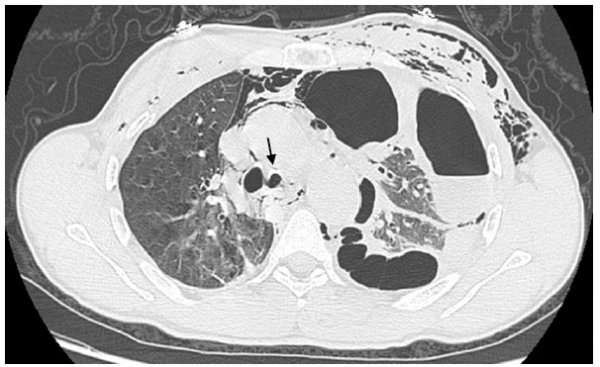

Mr T.A âgé de 47 ans, tabagique chronique, a été victime le 22 janvier 2011 d’un traumatisme thoracique fermé violent secondaire à un accident de travail à Errachidia, ville situé à 364 km de Fès. Il a été écrasé contre un mur par un camion benne transportant du sable, faisant marche arrière, avec un point d’impact principalement thoracique sans notion de perte de connaissance, ni d’hémoptysie. L’examen à son admission au service d’accueil des urgences, trouvait un patient conscient, polypneique à 20 cycles /min, la fréquence cardiaque était à 90 batt/min et la pression artérielle à 130/80 mmHg. L’examen du thorax, trouve des lésions ecchymotiques avec des douleurs à la palpation des côtes et un emphysème sous cutané. Les pouls périphériques étaient symétriques. L’auscultation pulmonaire trouvait une diminution du murmure vésiculaire du côté gauche. Le reste de l’examen était sans particularité. La radiographie du thorax a montré l’aspect d’un pneumothorax gauche cloisonné. Après la mise en condition, le patient est transféré aux urgences du CHU de Fès. Un scanner thoracique réalisé en urgence, a mis en évidence un pneumothorax gauche cloisonné, une contusion pulmonaire, des fractures costales gauches (du 3ème à la 6 ème côte), un emphysème sous-cutané, un pneumomédiastin et une rupture de la bronche souche gauche [fig1,2].